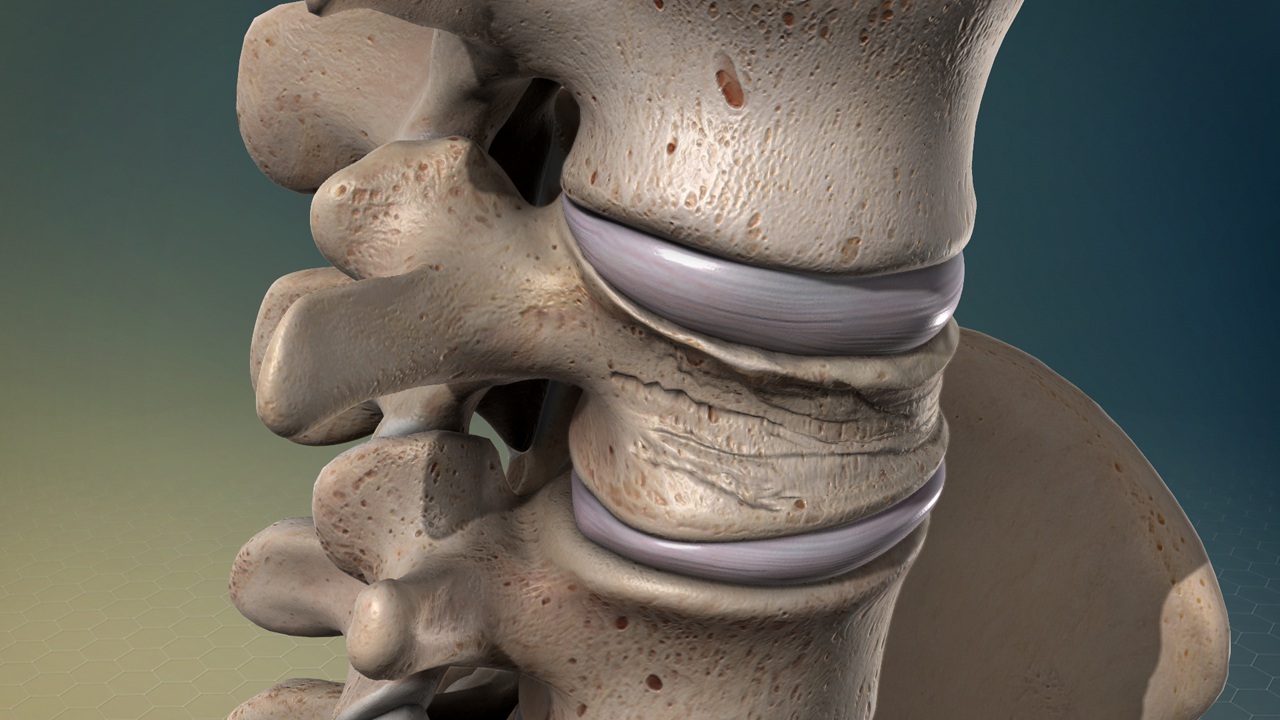

압축골절이란 무엇인가

압축골절은 말 그대로 뼈가 외부 압력에 의해 눌리면서 찌그러지듯 붕괴되는 형태의 골절을 의미합니다. 특히 척추에서 흔히 발생하며, 노인층이나 골다공증 환자에게 매우 빈번하게 나타나는 특징이 있습니다.

- 주로 척추에서 발생

- 뼈가 납작해지거나 높이가 줄어드는 형태

- 낙상이나 약한 충격에서도 발생 가능

- 골다공증 환자에게 빈도 높음

이 골절은 외형상 피부 손상이 없을 수도 있기 때문에 폐쇄성골절과 동시에 발생하는 경우가 많습니다. 즉, 압축골절은 골절 형태를 설명하는 개념입니다.